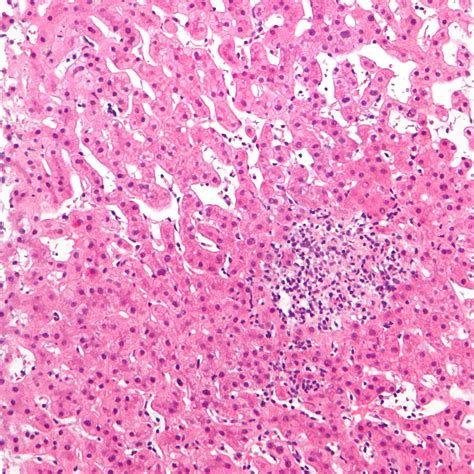

Understanding Hepatitis A

Hepatitis A is caused by the hepatitis A virus (HAV). It is one of several types of hepatitis viruses, including B, C, D, and E. Unlike some other forms of hepatitis, hepatitis A does not lead to chronic infection. It is typically a short-term illness that resolves on its own within a few weeks to a few months. However, it can be severe and even life-threatening in some cases, particularly for older adults and those with pre-existing liver disease.